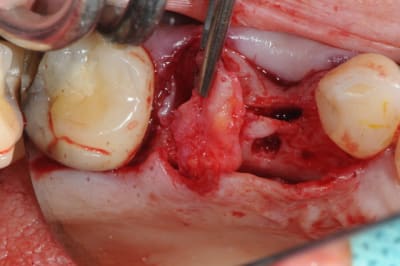

pour débuter ce post je propose un petit cas avec une ROG un comblement alvéolaire et un lambeau pédiculé pour fermer le site d'extraction.

au début incision supra crestal puis lambeau muco-périosté.

avec une simple lame 11 qui tranche le long de gencive palatine. évidemment c'est le plus dure à faire pour éviter de transpercer ou d'avoir d'un coté ou de l'autre une épaisseur trop faible.